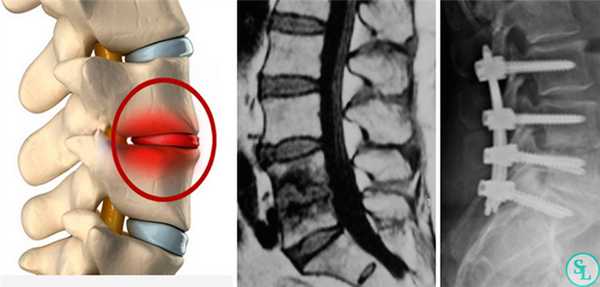

Дискэктомия (удаление разрушенного диска) и корпэктомия (удаление фрагмента тела позвонка) позволяют полностью очистить пораженные ткани. Внедрение распорочных трансплантатов (вырезанных из костных структур, взятых в ребрах или гребне подвздошной кости) позволяет хрящевым тканям начать восстанавливаться, а фиксирующие позвоночный столб титановые конструкции временно снимут нагрузку на пострадавшие позвонки. Реабилитация занимает от 3 месяцев до полугода. Прогноз на излечение спондилодисцита всегда положителен.

Чаще всего пациентам проводится удаление межпозвоночных грыж и установка на место резецированных межпозвонковых дисков специальных кейджей. Только такой комплексный подход обеспечивает полное устранение болевого синдрома и надежную профилактику их возникновения в связи с поражением этого же позвонково-двигательного сегмента в будущем.

При заднем типе хирург получает возможность проводить манипуляции на позвоночнике, рассекая кожу, фасции и раздвигая в стороны глубокие мышцы спины. Это позволяет меньше травмировать ткани, поэтому реже приводит к возникновению нежелательных последствий и обеспечивает более легкое и быстрое протекание реабилитационного периода. Проведение спондилодеза через задний доступ в подавляющем большинстве случаев стало возможным благодаря созданию титановых кейджей, в составе которых присутствует костная крошка. Это специальные имплантаты, устанавливаемые вместо удаленных межпозвонковых дисков. Они пришли на смену костным или искусственным имплантатам и значительно повысили безопасность и эффективность хирургического вмешательства.

Дискэктомия (удаление разрушенного диска) и корпэктомия (удаление фрагмента тела позвонка) позволяют полностью очистить пораженные ткани. Внедрение распорочных трансплантатов (вырезанных из костных структур, взятых в ребрах или гребне подвздошной кости) позволяет хрящевым тканям начать восстанавливаться, а фиксирующие позвоночный столб титановые конструкции временно снимут нагрузку на пострадавшие позвонки. Реабилитация занимает от 3 месяцев до полугода.